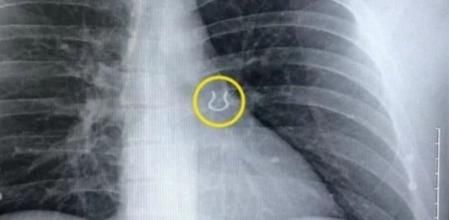

Una radiografía ha revelado el inusual objeto encontrado en el lóbulo superior del pulmón

El último hallazgo extraño que han encontrado unos médicos en el interior del cuerpo de un paciente ha sido un piercing de la nariz perdido en el lóbulo superior del pulmón izquierdo del paciente. Un trozo de metal que el hombre había perdido cinco años atrás.

Una vez en el hospital, los médicos le realizaron la radiografía que desveló cuál era el objeto que estaba obstruyendo su respiración: “El doctor entró y me enseñó la imagen de rayos X y dijo: ‘¿Esto te parece familiar?'”, señalaba el paciente en Odditycentral mientras añadía que “Estaba como, '¡Tiene que ser una broma!' He estado buscando eso durante mucho tiempo. No sabía lo que estaba pasando, pero nunca hubiera pensado que eso podía estar ahí”.